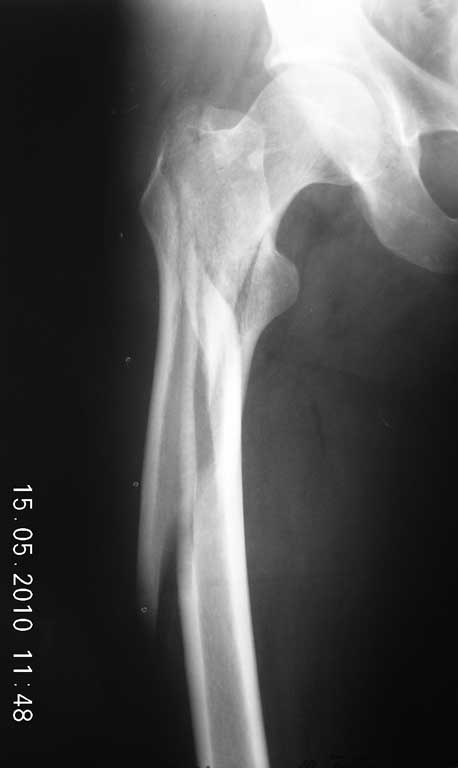

молодой мужчина. травма производственная. падение с высоты 2метра на бок. перелом

распространяется на медиальный и латеральный кортекс. какой имплантат применить в данном

случае оптимально?